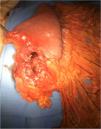

Surgery was programmed, and it revealed thickening of the gastric wall, which was ulcerated, perforated, and sealed in the direction of the liver and gallbladder (fig. 1). Subtotal gastrectomy and cholecystectomy were carried out and liver biopsy was taken at the site of probable tumor invasion due to contiguity in segment V. The histopathologic study of the intraoperative and definitive sample reported ulcerated and perforated gastric diffuse large B-cell lymphoma (fig. 2A-B). The patient had satisfactory postoperative progression and was released to continue outpatient follow-up and treatment.